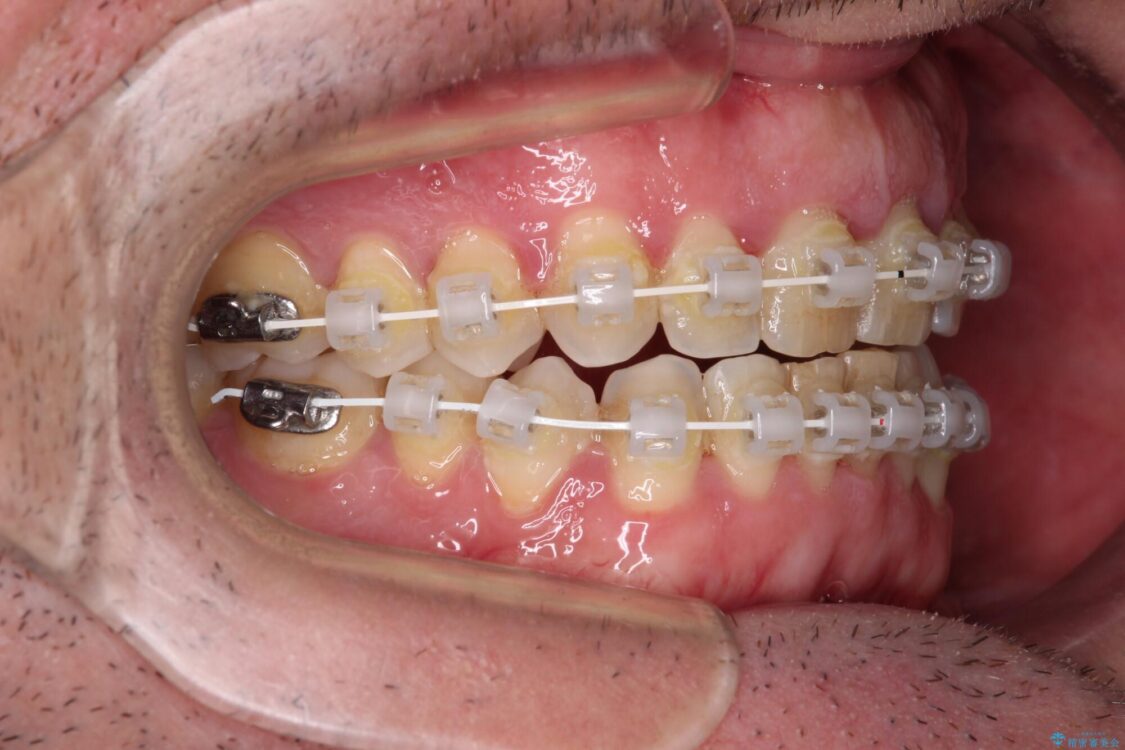

治療途中

• 前歯でものを噛みきりたい 目立たない装置でのワイヤー矯正 治療途中画像